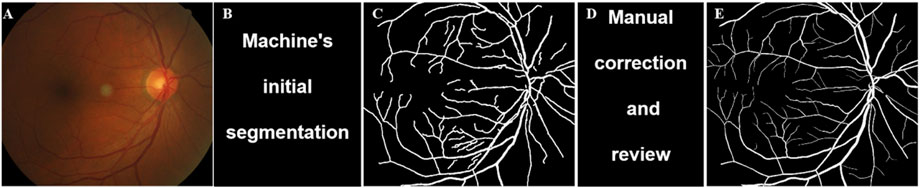

In this paper, the fundus image intelligent analysis software—EVisionAI is used to intelligently process the fundus image (Xu et al., 2019). The software is designed based on the bionic mechanism of human vision and deeply integrates image processing technologies such as computer vision and deep learning, which first performs Regions of Interest (ROI) extraction, denoising, normalization, and enhancement operations to remove invalid areas such as the image background and reduce image noise and image differences (Xu et al., 2019; Zhang et al., 2022). Then it combines the deep learning network model with the edge extraction algorithm based on the visual attention mechanism to finely identify and segment the features of the optic disc, and retinal blood vessels, respectively (Zhang et al., 2022). This study systematically presents several key technical components using an AI-based quantitative analysis approach, encompassing the vascular labeling workflow (Figure 1), the segmentation results (Figure 2), as well as quantitative parameterization indicators such as vascular diameter (Figure 3), tortuosity (Figure 4), and branch angle (Figure 5). Based on the segmentation results, the retinal vascular and optic nerve head (ONH) parameters, such as vascular fractal dimension (VDf), vascular caliber (VC), vascular tortuosity (VT), vascular density (VD), vascular branching angle (VBA), area of optic disc, arteriole-to-venule ratio (AVR), and cup-to-disc ratio (C/D), were measured. This comprehensive digital characterization aims to provide a detailed description of the color fundus photographs and their underlying structures. The computation of vascular fractal dimension (VDf) mainly involves the following steps: (1) retinal image preprocessing, (2) extraction of retinal blood vessels, and (3) calculation of the VDf. The accuracy of feature recognition for each result was ≥0.96, sensitivity ≥0.85, and specificity ≥0.96.

Figure 1

Panel A shows a retinal image with visible blood vessels. Panel B displays the text

Figure 1. Vascular labeling process of fundus image. The specific process includes: (A) Original image; (B) Machine’s initial segmentation; (C) Preselected vascular regions; (D) Manual correction and review; (E) Final labeled sample.